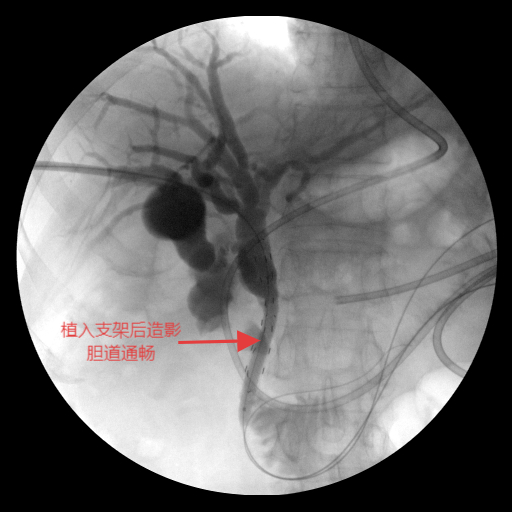

手术在C型臂透视精准引导下开展:团队沿原PTCD通道送入“头发丝”细的导丝,首次穿刺即成功,精准选取最优胆道入路以规避组织损伤;导丝跨越梗阻段时,团队密切协作避免反复抽拉引发肠道逆行感染。针对外压性病灶导致的狭窄,先以球囊扩张狭窄部位,再将装载I-125的自膨式可载粒子胆道支架精准送入胆总管梗阻段并缓慢释放。术后造影显示,支架扩张效果良好,造影剂可通畅流入十二指肠,患者生命体征平稳。

置入自膨式可载粒子胆道支架